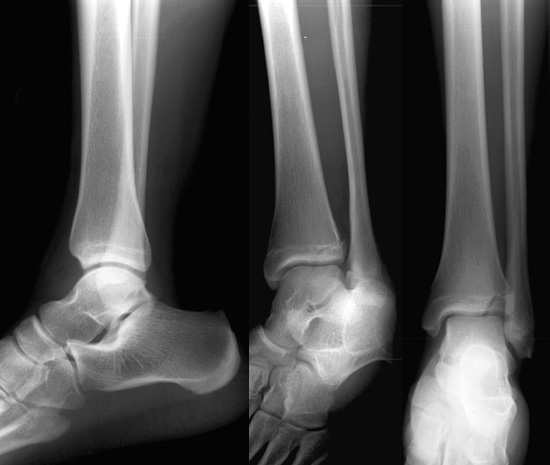

• Look for a vertical fracture line extending from the distal articular surface upward to the lateral cortex of the tibia.

Look at the radiographs below. Can you identify the fracture?

Lateral, oblique and AP views